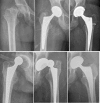

Background: Femoral neck fractures in the elderly are frequent, represent a great health care problem, and have a significant impact on health insurance costs. Reconstruction options using hip arthroplasty include unipolar or bipolar hemiarthroplasty (HA), and total hip arthroplasty (THA). The purpose of this review is to discuss the indications, limitations, and pitfalls of each of these techniques.

Results: THA yields the best functional results in patients with displaced femoral neck fractures with complication rates comparable to HA. THA is beneficially implanted using an anterior approach exploiting the internervous plane between the tensor fasciae latae and the sartorius muscles allowing for immediate full weight-bearing. Based on our findings, bipolar hemiarthroplasty, similar to unipolar hemiarthroplasty, cannot restorate neither anatomical nor biomechanical features of the hip joint. Therefore, it can only be recommended as a second line of defense-procedure for patients with low functional demands and limited live expectancy.

Conclusions: THA is the treatment of choice for femoral neck fractures in patients older than 60 years. HA should only be implanted in patients with limited life expectancy.